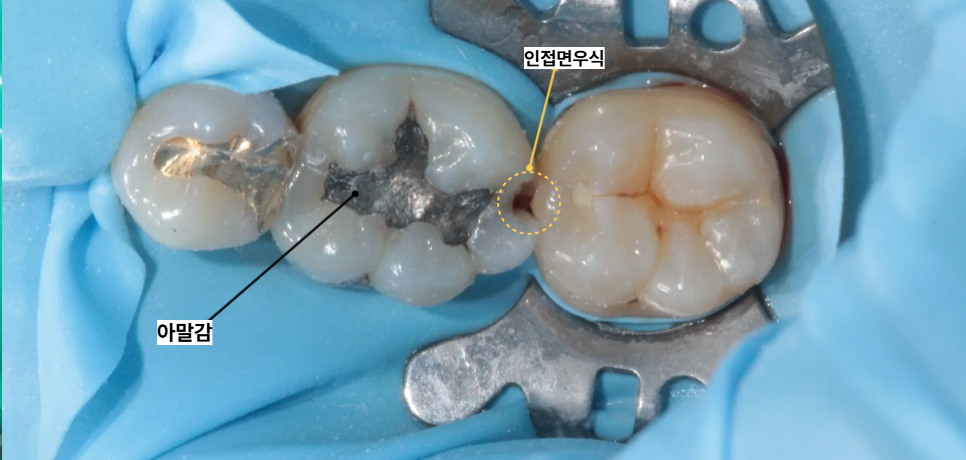

세이지치과에서 진행한 첫 번째 환자분은 과거에 아말감으로 치료를 받았던 부위에 문제가 생겨 내원하신 경우입니다. 정밀한 검진 결과 기존에 충전되어 있던 아말감 주변부로 2차 우식이 진행되고 있었으며 치아와 치아가 만나는 인접면 부위에도우식이 확장된 상태였습니다.

아말감은 시간이 지나면 끝부분이 부서지거나 틈이 생기기 쉬운데 이 틈을 통해 세균이 유입되어 내부에서 다시 부식이 일어난 것입니다.

우선 기존에 있던 아말감 재료를 깨끗하게 제거한 뒤 내부에 진행된 이차 우식 부위와 인접면의 충치 조직을 세밀하게 삭제하였습니다.